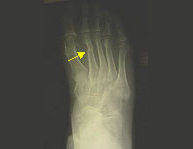

La región del pie es un conjunto de huesos y articulaciones con numerosas funciones entre las que destaca el soporte de todo nuestro peso y la deambulación (caminar). Es una región sometida a carga constantemente salvo cuando no caminamos, es por ello que su rápida recuperación es indispensable para poder desplazarnos de un lugar a otro. El pie a su vez se divide en tres partes: retropié, mediopié y antepié y cada región sufre sus lesiones características. En el deporte las lesiones del pie son muy frecuentes debido a la implicación de éste en la mayor parte de ellos. Por lo general las fracturas del pie responden correctamente al tratamiento conservador reservando la actitud quirúrgica a aquellas lesiones complejas irreparables sin cirugía.